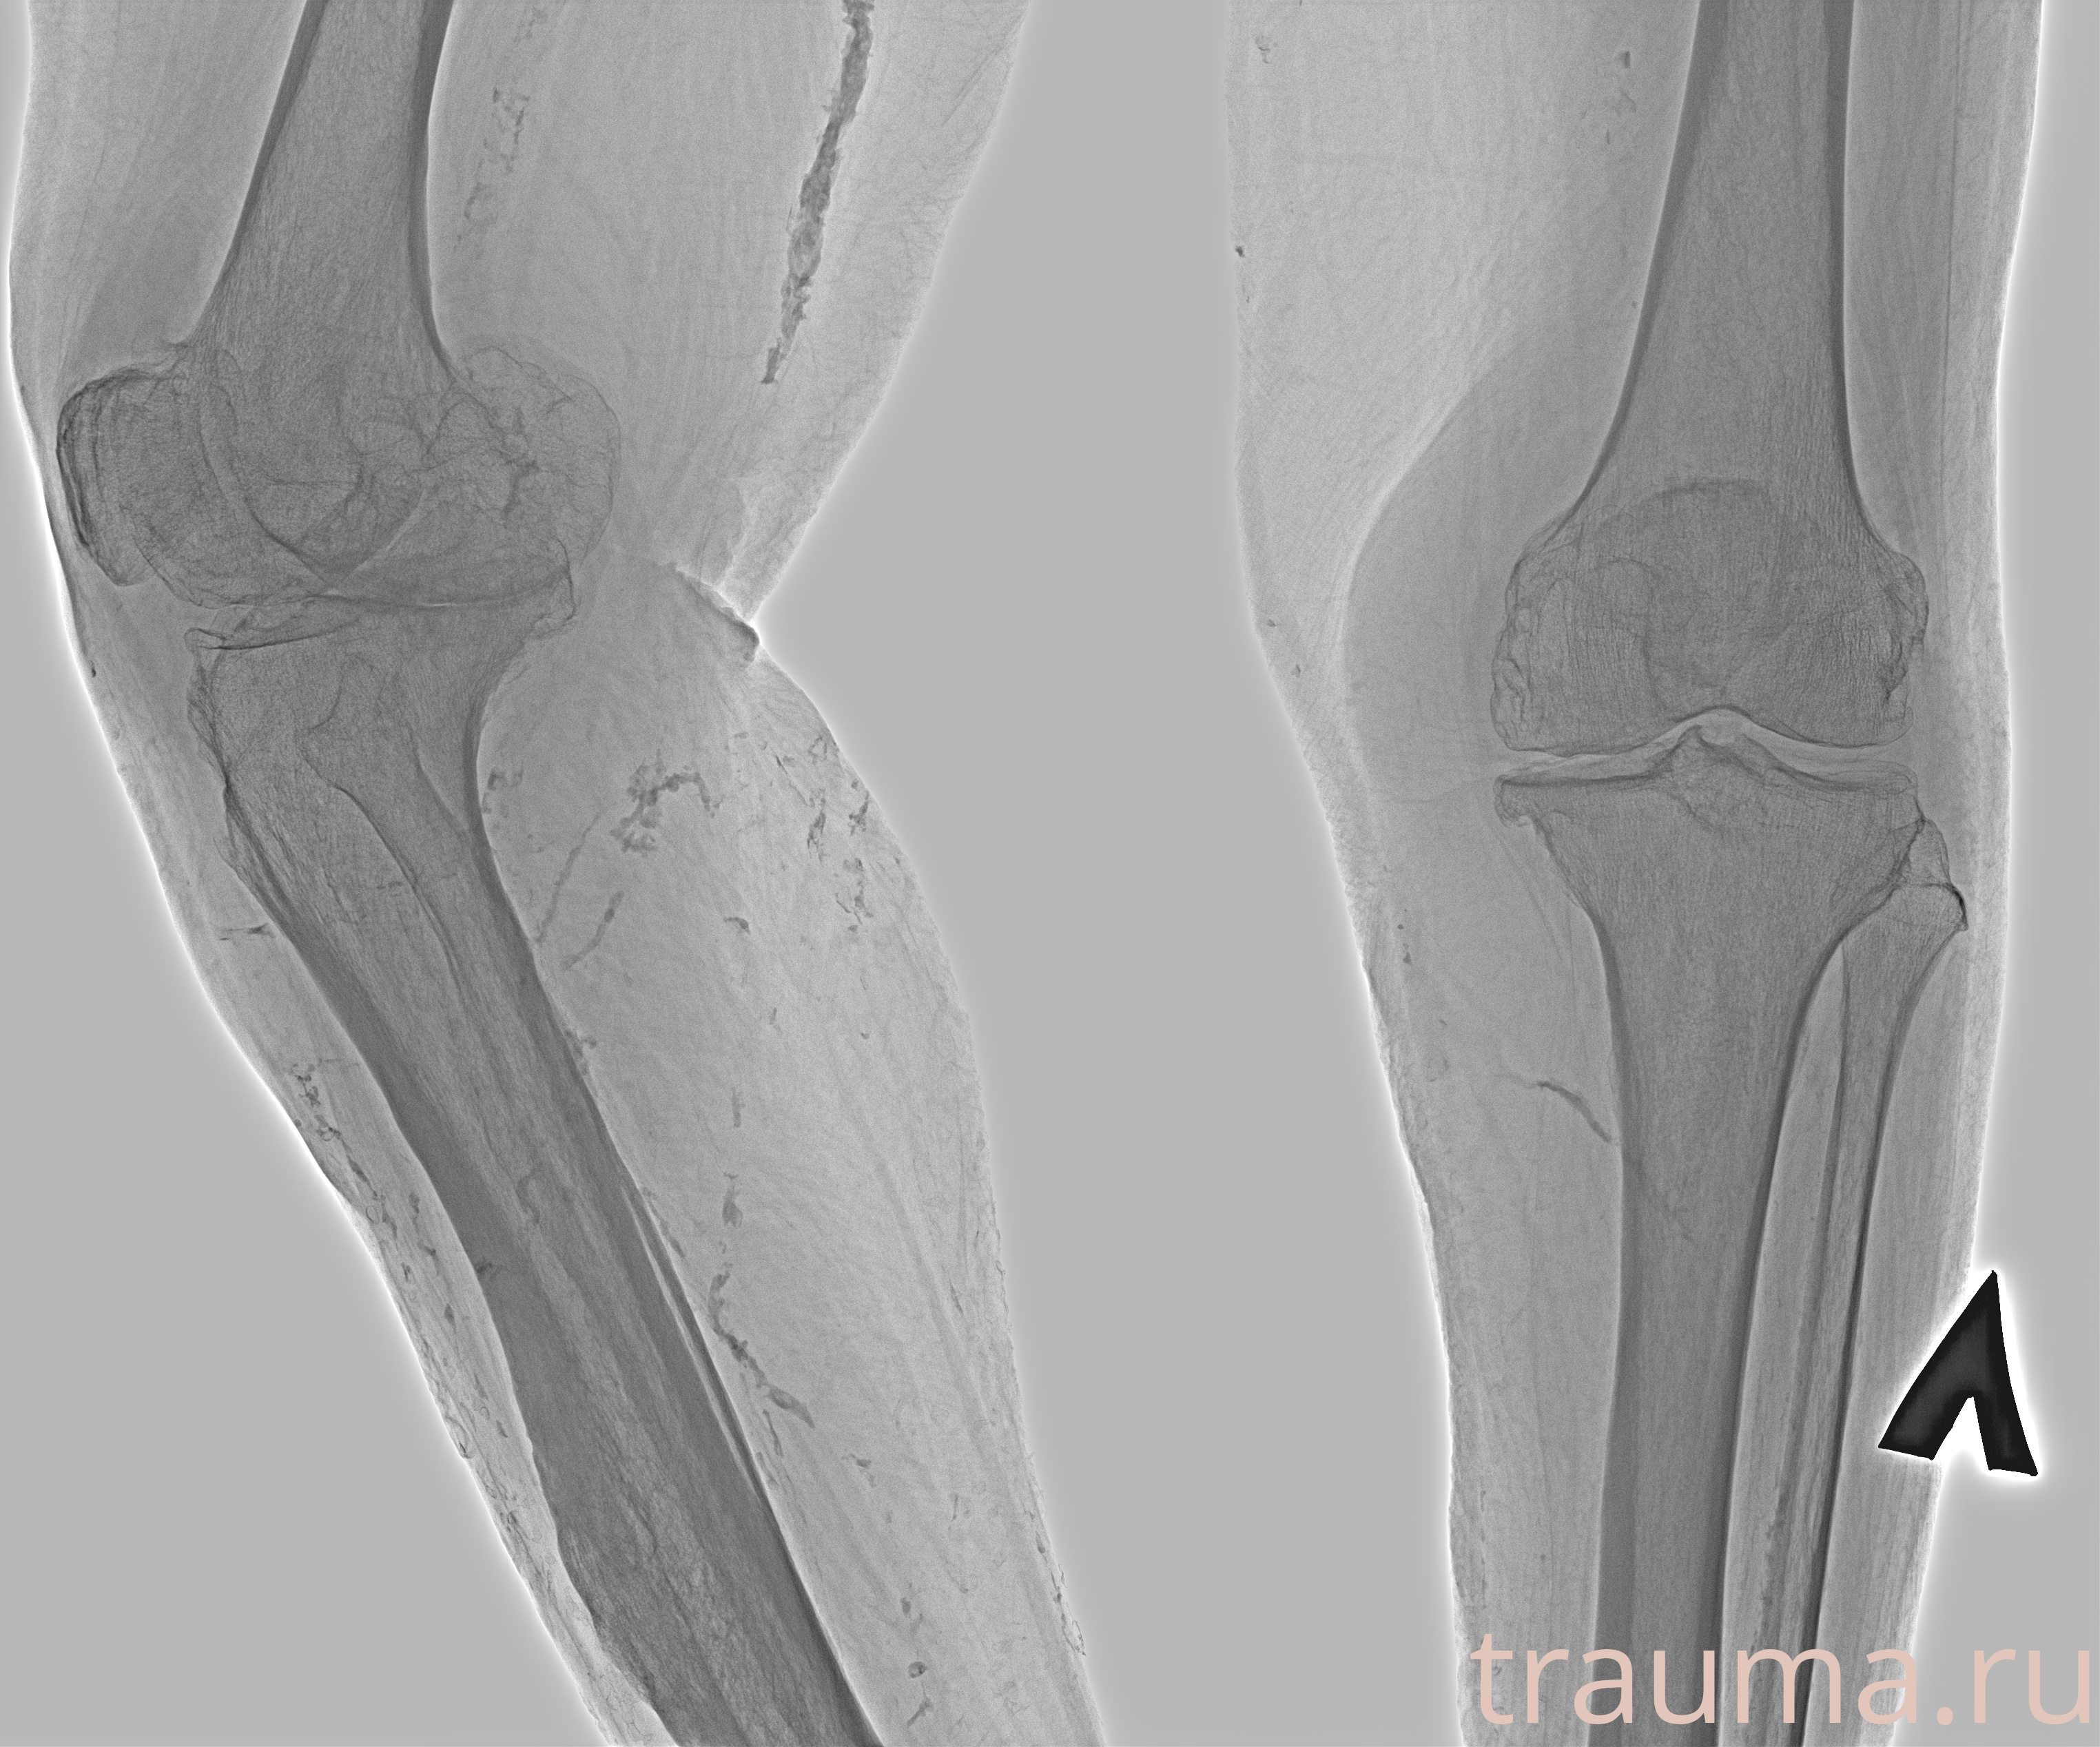

Рентгенограммы

Рентген на дому: по вашему адресу приезжает врач-рентгенолог, травматолог-ортопед с мобильным рентгеновским аппаратом, проводит диагностику травмы или заболевания, делает необходимые рентгенограммы, дает рекомендации по дальнейшему лечению. Получить качественные снимки в домашних условиях возможно благодаря уникальной методике, разработанной МосРентген Центром для института  Склифосовского